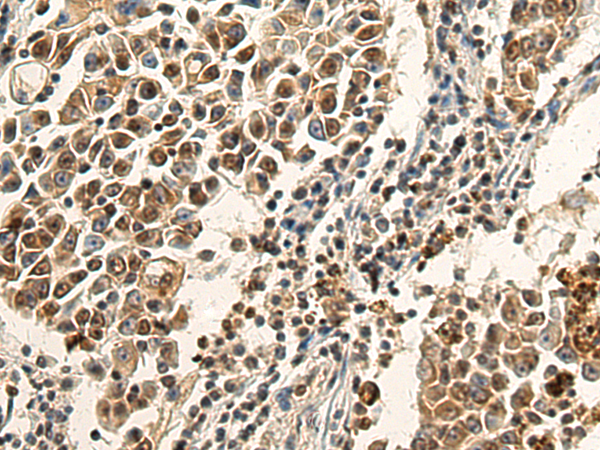

分类: 科研抗体货号: P10348别名:应用: IHC反应种属: Human, Mouse